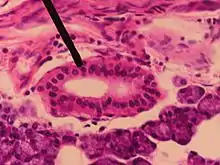

Section of submaxillary gland of kitten. Duct semidiagrammatic. X 200.

Section of portion of mamma.